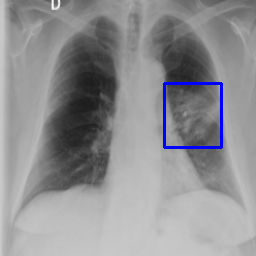

4.1.3 Derivable Task

After fine-tuning the target classification task, we can visualize the output of the target task by simply computing the gradient of the winning class with respect to the last convolutional layer of the target task as described in Chen et al. (2018b). Then, we compute the average, weigh it against the output of this layer, and normalize it between 0 and 1 to generate the heatmap. This map visualizes discriminative areas the head looks at when classifying into normal and abnormal. As this visualization task relies on the output of the classification head, we can define it as a task derivable from the target task. Figure 7 presents the visualization of the abnormality classification task.